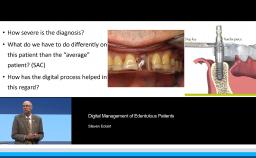

Esthetically challenging cases often involve two or more specialized clinicians working together throughout the treatment phases. This step-by-step cooperation is crucial to arriving at a pleasing esthetic result. This lecture presents various situations of compromised teeth and implants in which an interdisciplinary approach and modification are indicated. The rationale for predictable treatment and some clinical tips are also discussed.